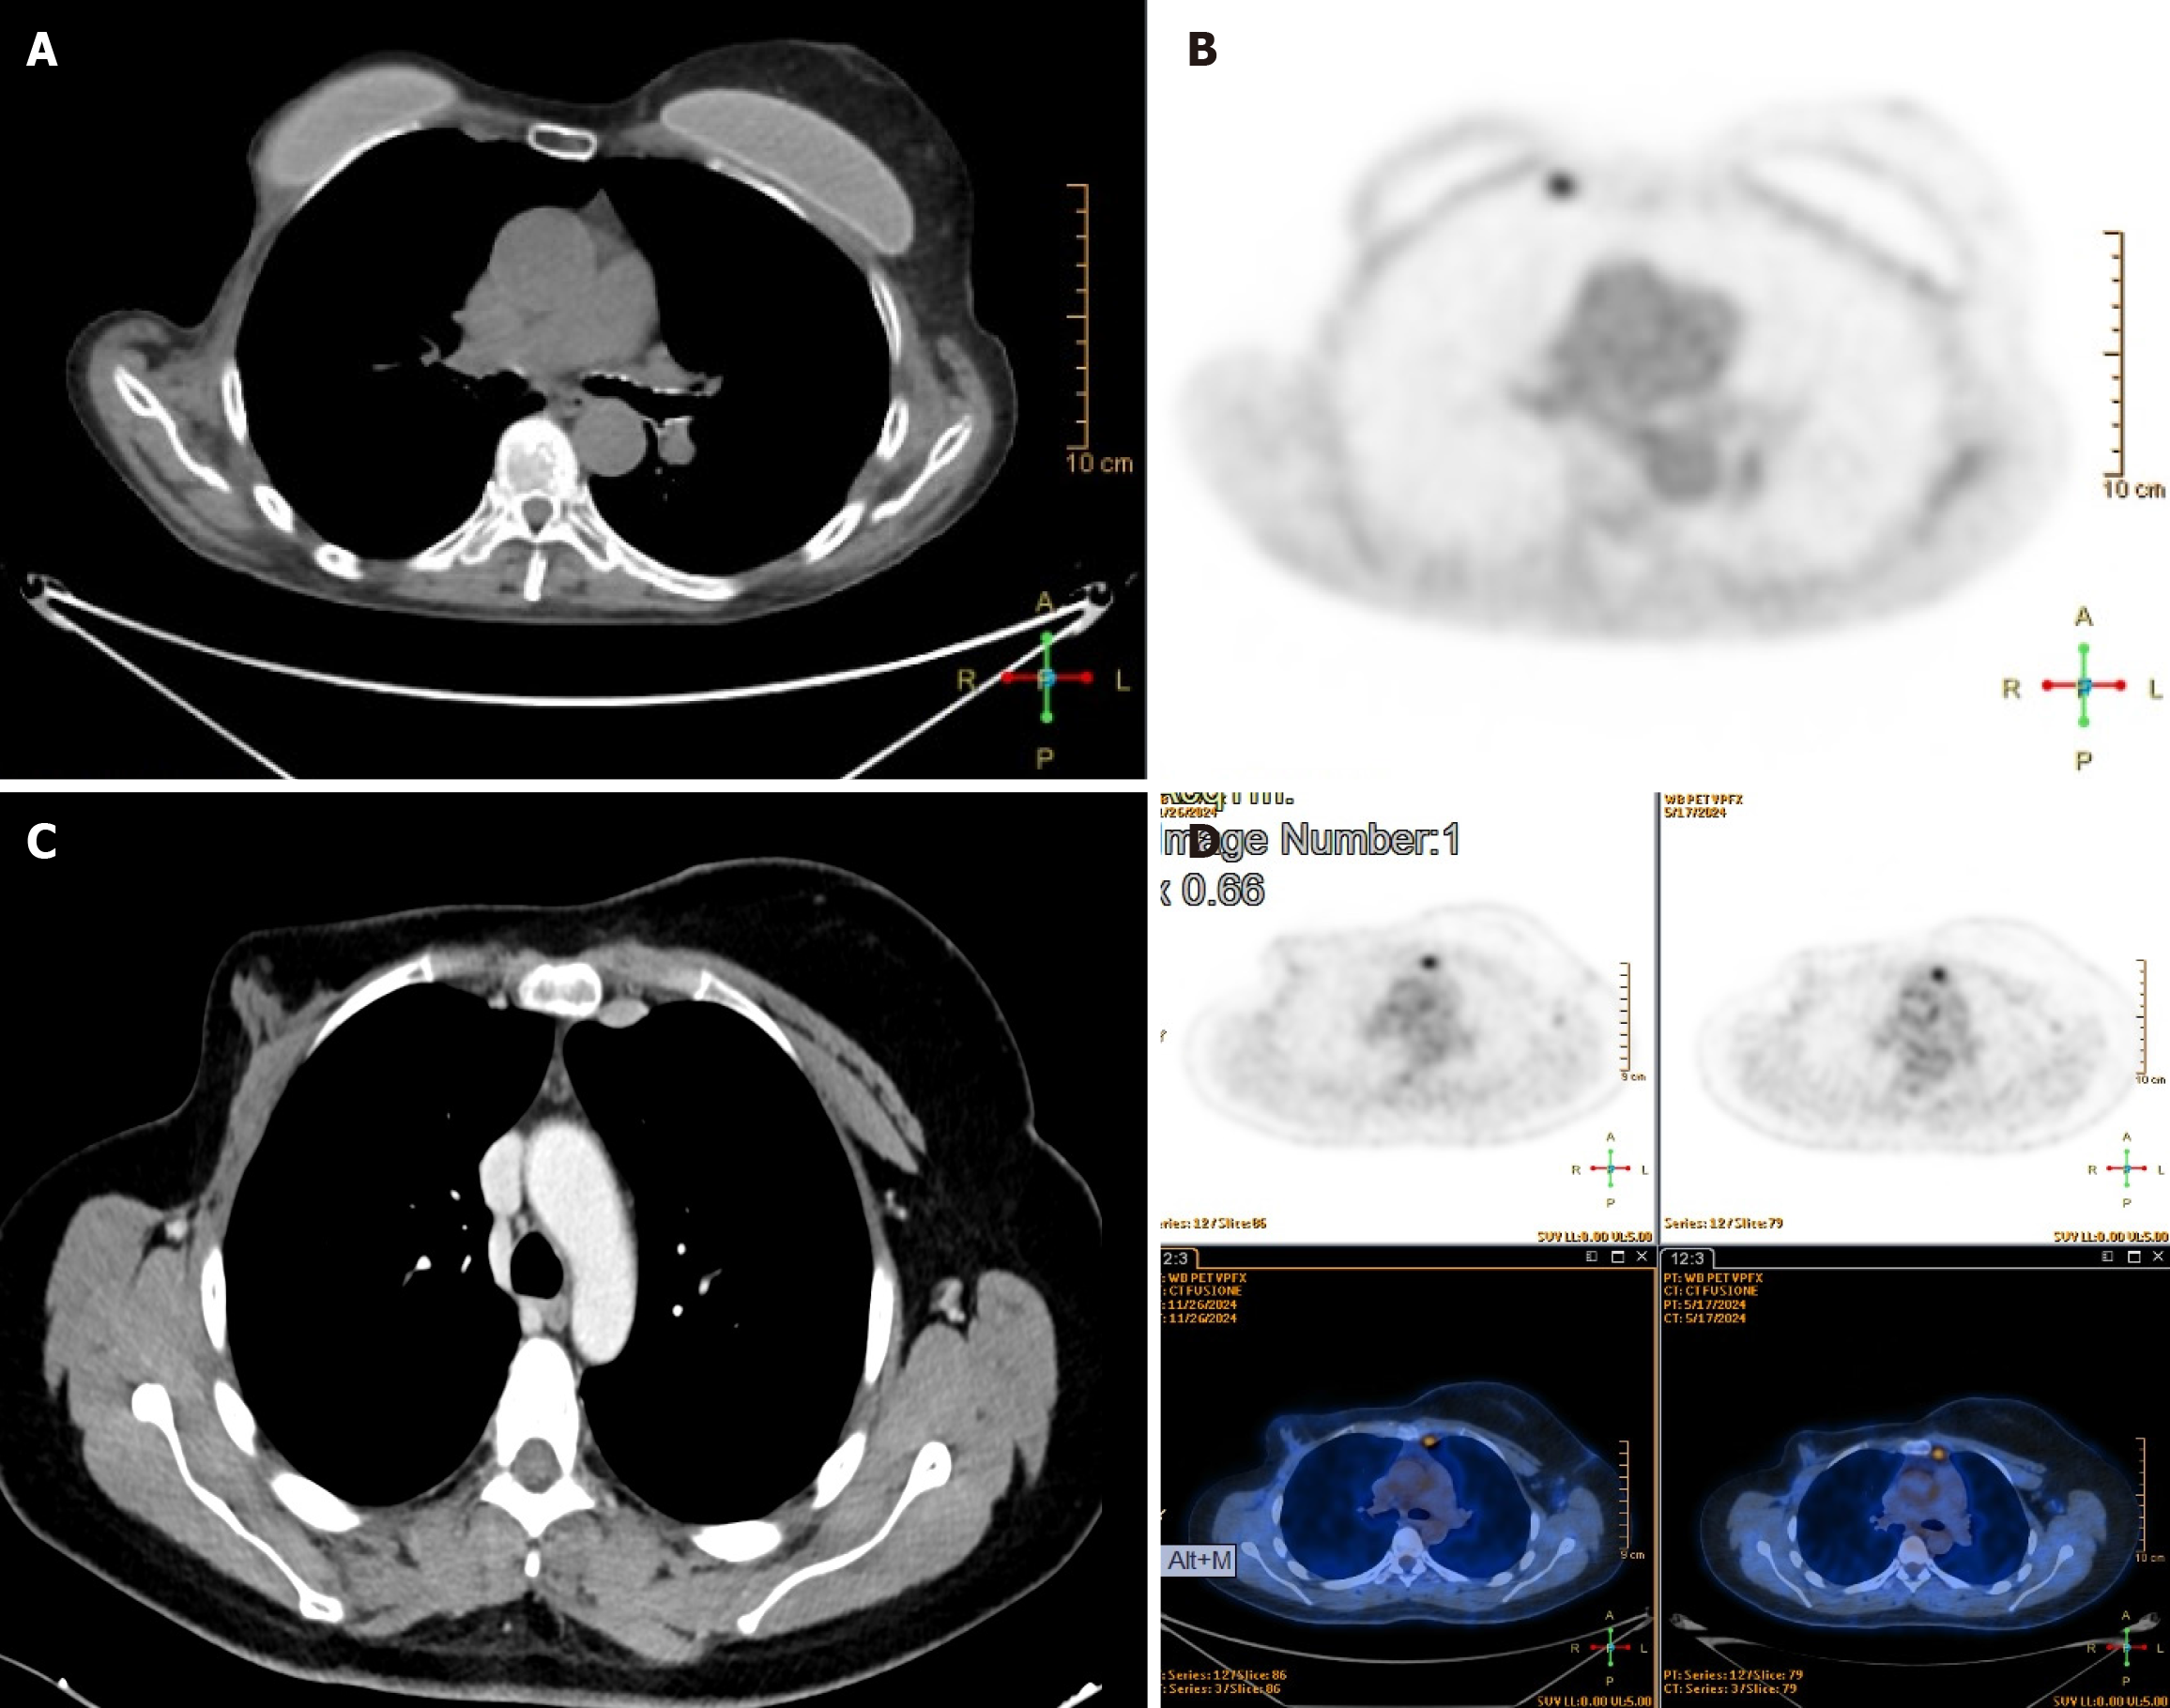

Figure 2 Chest computed tomography scan and positron emission tomography scan.

A and B: Left internal mammary lymphadenopathy; C and D: Right internal mammary lymphadenopathy.